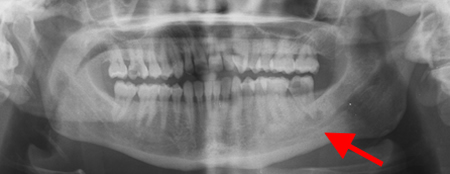

Panoramic radiograph showing periapical abscess related to the lower-left second molar

From the personal collection of Melanie S. Lang and Thomas B. Dodson